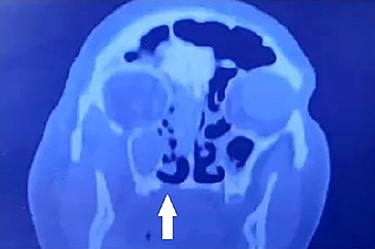

Contrast-enhanced CT of the sinuses was requested on an urgent basis which showed a picture of right-sided pansinusitis with only mucosal thickening of the left maxillary sinus. In addition, there was radiological bony erosion of the floor of nose on the right side (Fig. 3). No orbital involvement was noted.

Coronal CT showing bony erosion of the right side of the hard palate (white arrow) with ipsilateral maxillary and ethmoid opacification.